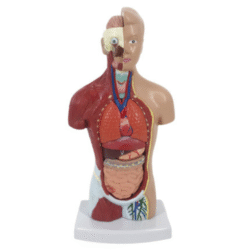

ATL-12 MALE MUSCLES FIGURE 2 PARTS

The model is an anatomically accurate representation of the human anatomy, complete with superficial and deep musculature, the digestive system, lymphatic system, respiratory system, urinary system, circulatory system, endocrine system, and nervous system. Our model has removable organs and dissectible features for a complete educational experience.

Classification:

Skeleton Models(human bone, muscle, etc.)